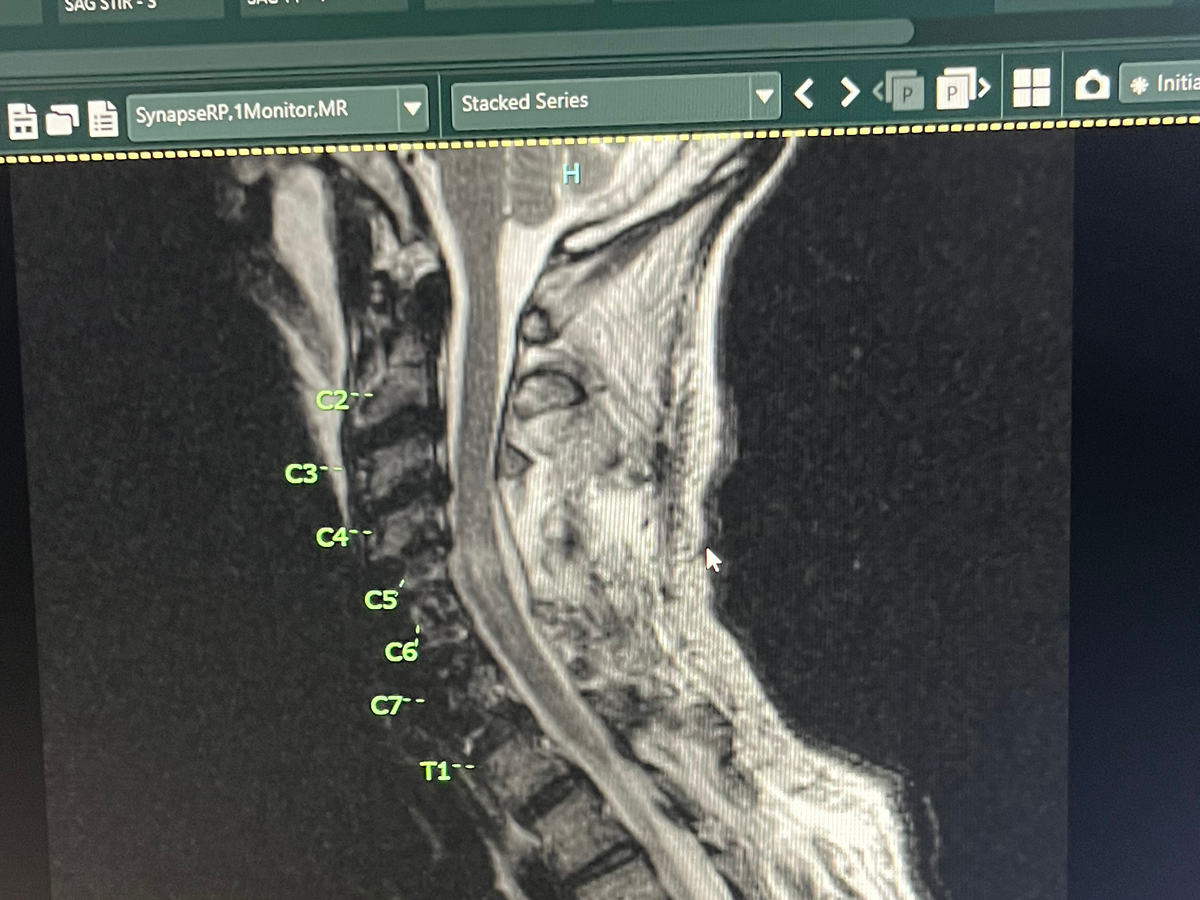

On the day of a routine medical procedure fusing together C4 C5 and C6, previously C5 C6 and C7 were fused during the procedure C3 as well needed to be fused as a result of this, complications occurred that resulted in spinal cord injury and loss of motor function. Mr. Fisher is under the care of his treating physicians and specialty consultants. Medical records and procedure summaries have been secured and are being reviewed by his care team and independent specialists to define the cause, the precise neurologic level and extent of injury, and the timelines for decision points about experimental therapies and rehabilitation.

• Before any experimental treatment, protocol eligibility and medical clearances are required: imaging review (MRI/CT), electrophysiology testing, infectious disease screening, and comorbidity clearance. These tests are being prioritized.